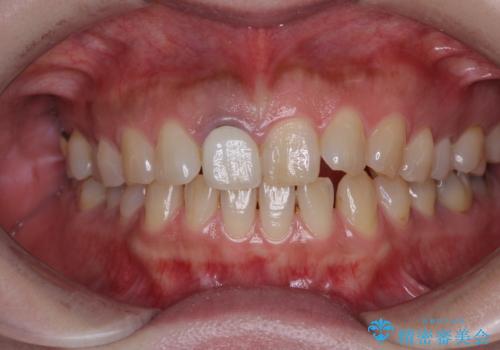

- セラミッククラウンが白すぎる前歯と、放置している奥歯を気にして来院された患者様です。

前歯のセラミッククラウンは将来ホワイトニングをするつもりで白くしたものの、それほど白くならず、ホワイトニングも面倒くさいとのことで白すぎる印象となっていました。

前歯のセラミッククラウンは周りの歯と調和させるためにオーダーメイドタイプのものをおすすめしましたが、元が白すぎていたため、概ね色合いが合えば大丈夫であるとのことで、既製パターンの色調で仕上げました。